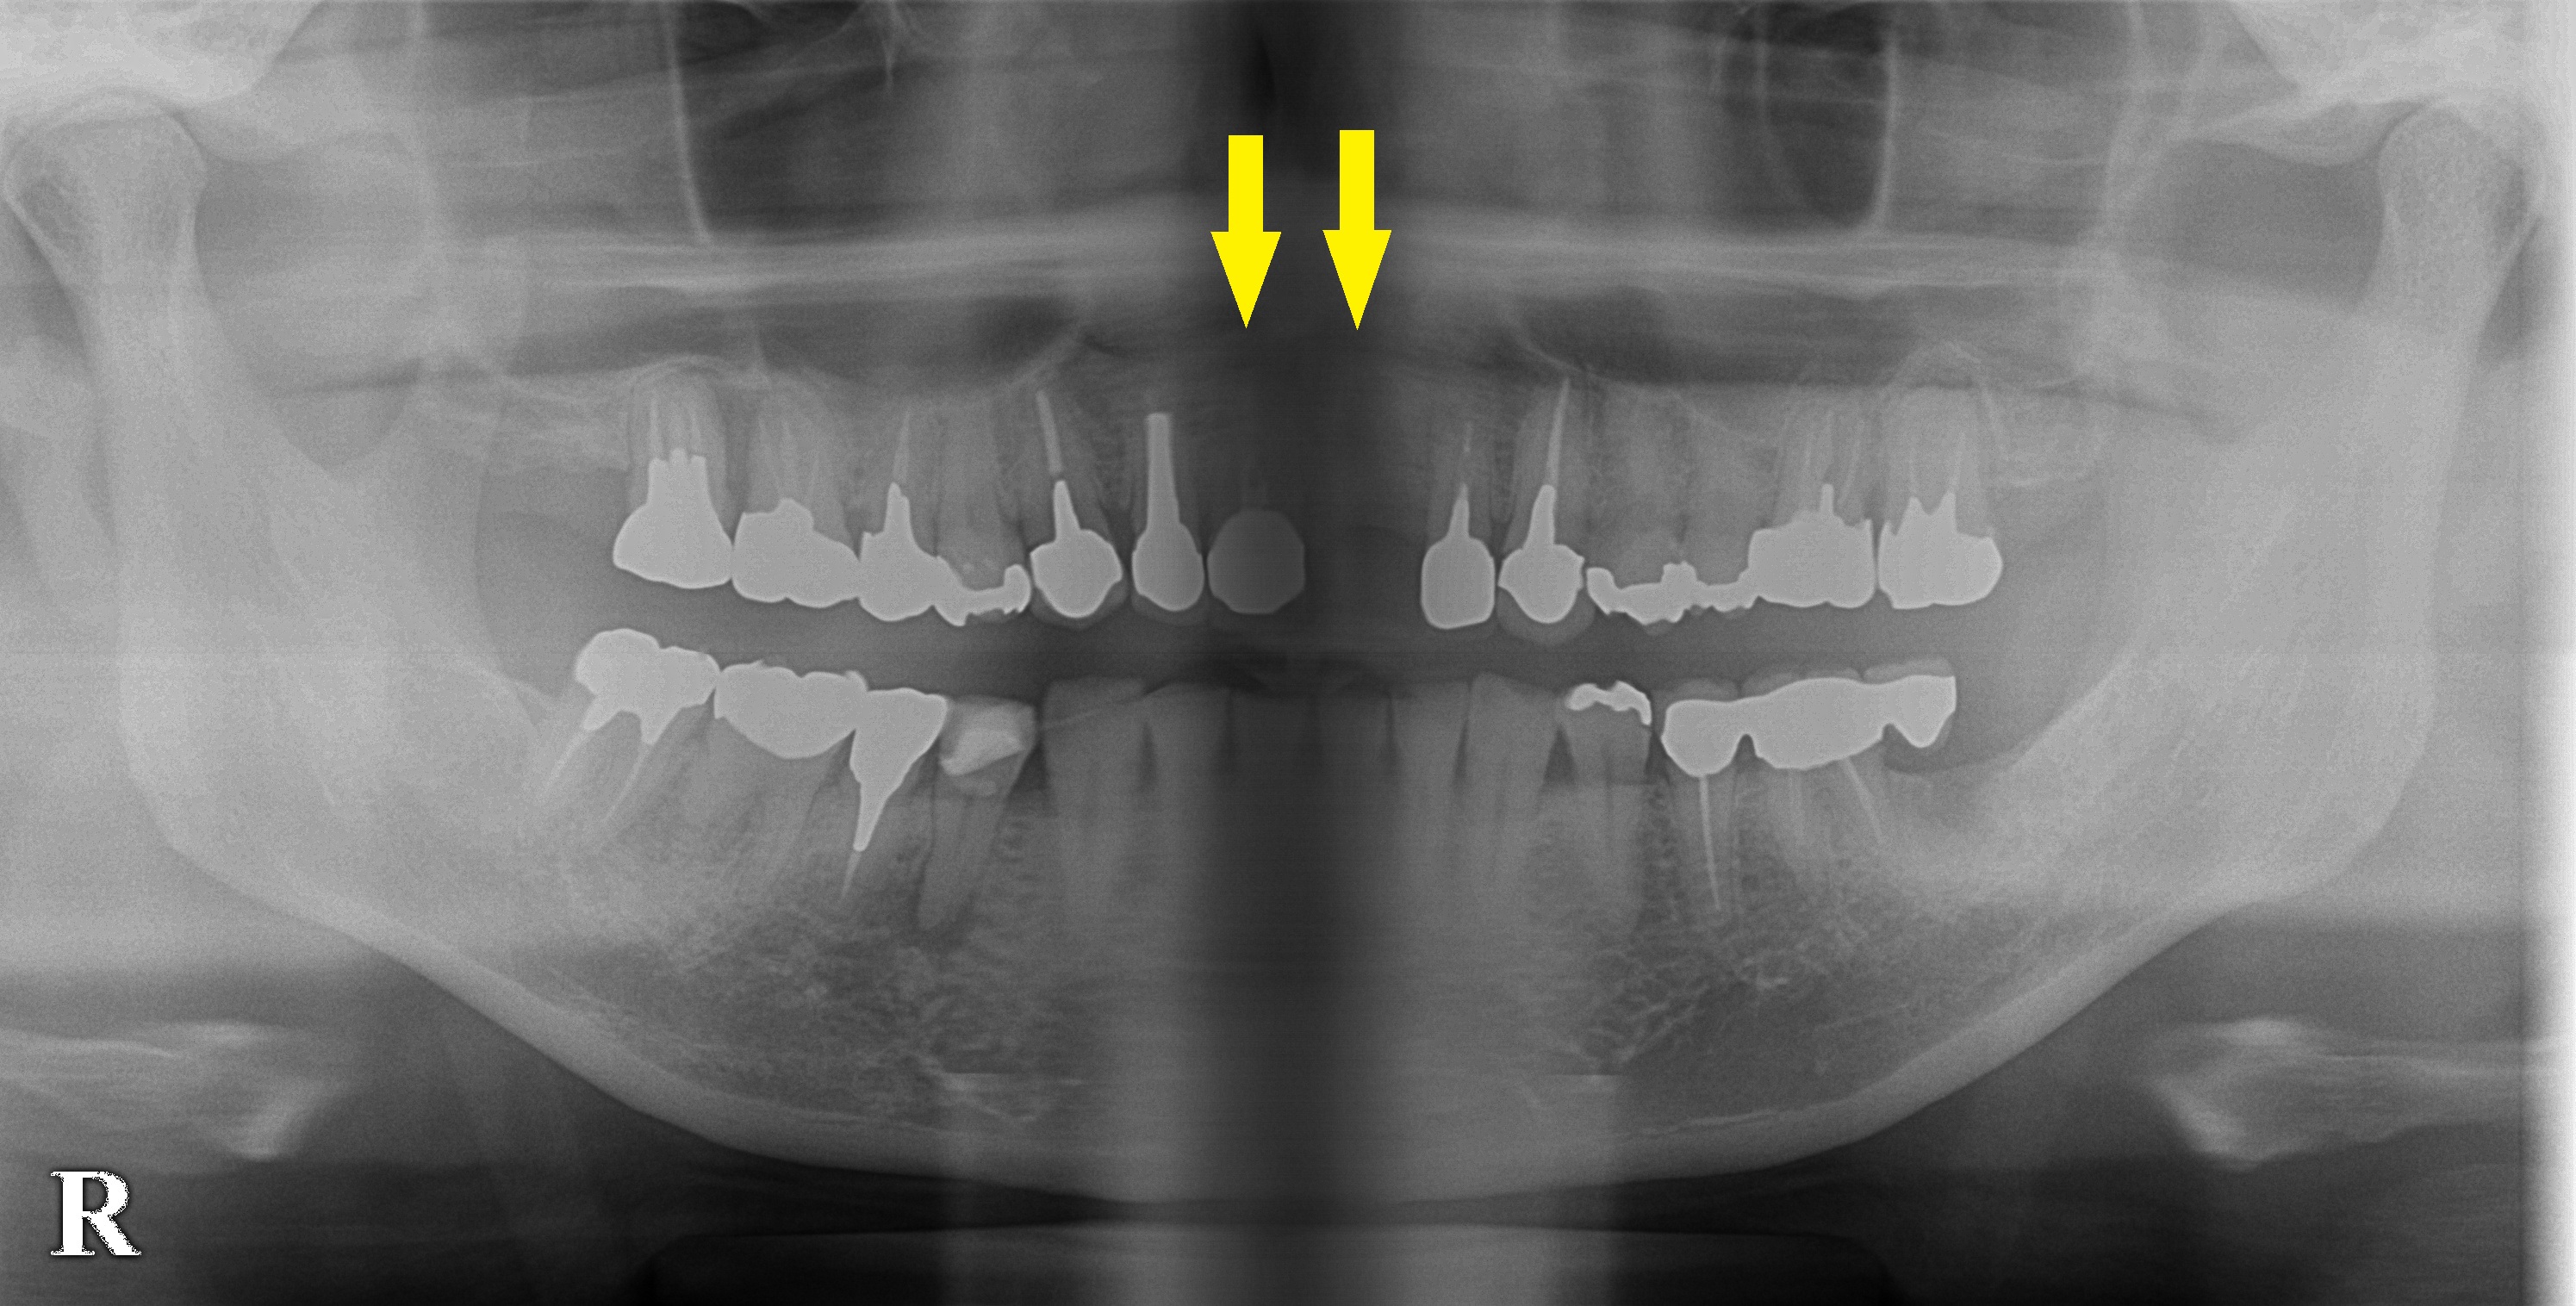

上顎前歯が抜け、インプラント治療を希望されて来院されました。

左上顎の前歯が抜けてしまっていたのですが、

右隣りの前歯も状態が悪く抜歯となりました。

抜歯後、CTを撮影してみると、外側に陥凹した形をしており、骨の厚みも不十分でした。

そこで、本日、インプラント埋入と同時に、外側に人工骨を補填するという方法で骨造成を行いました。